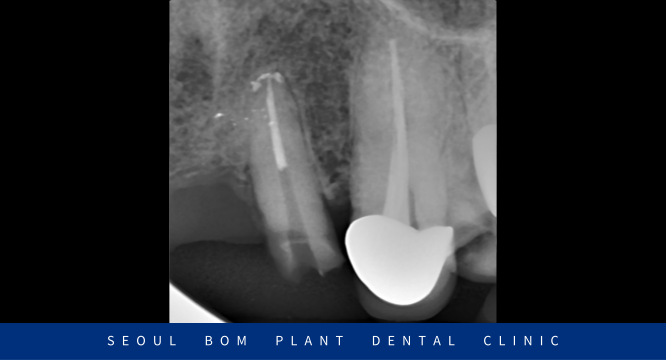

기존 보철물을 제거해 보았더니

위턱 왼쪽 두 번째 앞니(#22)의 치아머리가

이미 파절되어 있는 상태였으며,

발치를 하기에는 아깝다고 판단되어

신경치료를 통해 치아를 보존하는 치료를 진행하기로 하였습니다.

감염된 신경조직을 제거한 뒤 깨끗하게 소독하는 과정을 거쳤으며

환자분께서 별다른 증상이나 통증이 없으신 것을 확인한 뒤

신경을 제거한 근관내부에 치과재료로 치근 끝까지

꼼꼼하게 채워 넣으면서 신경치료를 마무리하였는데요.